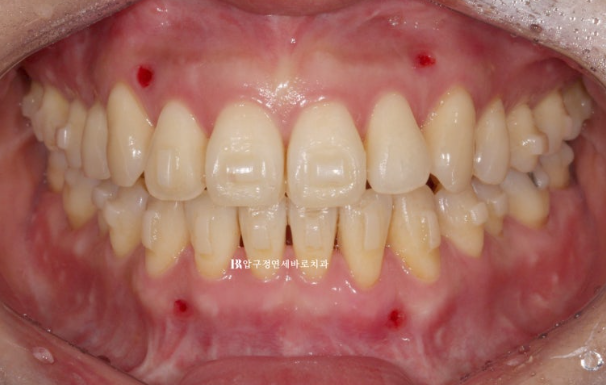

양악수술 교정을 위해 내원하신 분.

치아 중심선이 틀어져 있는 만큼 턱의 비대칭이 있고

23.01

어금니 뿐 아니라 앞니가 거꾸로 물리는 반대교합이므로 골격성 3급 부정교합으로 진단이 되었습니다.